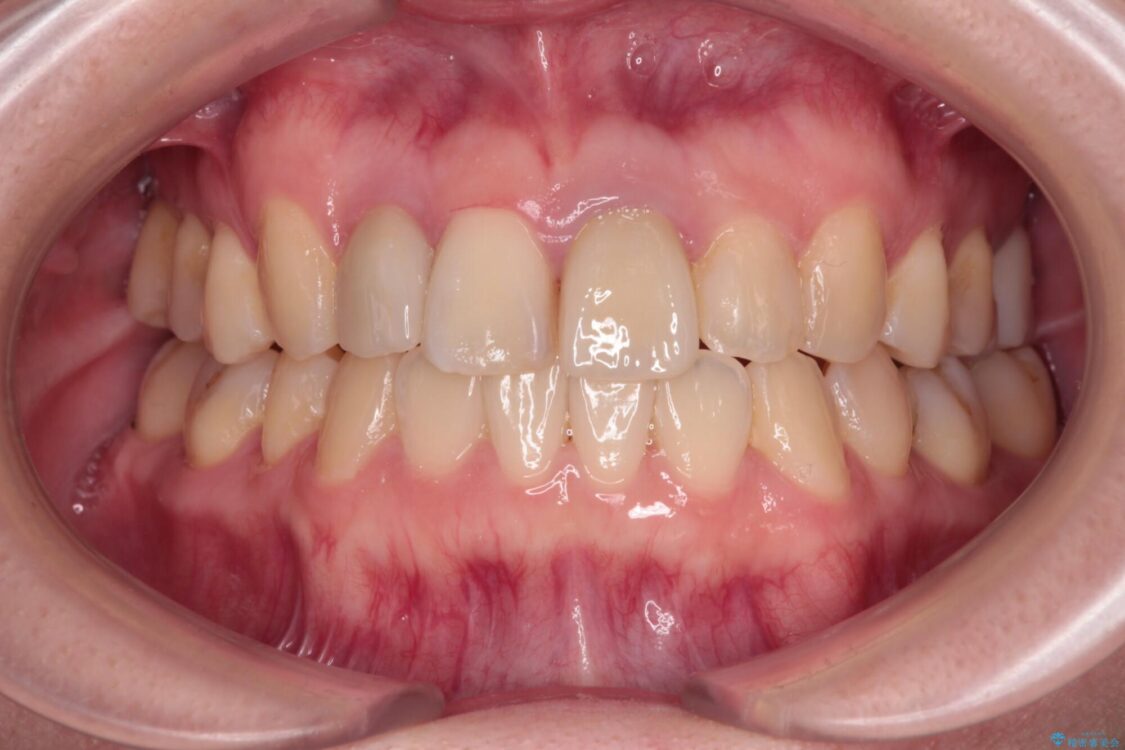

治療後

• 虫歯治療ついでに歯並びの後戻りを改善 インビザラインによる矯正治療 治療後画像

後戻りは軽度であり、インビザラインにて歯列を整え、その後にオールセラミッククラウンにて補綴治療を行うこととしました。

治療後について

ご家庭やお仕事の都合で通院が途絶えた時期があり、治療は長期間となりましたが、無事に終えることができました。